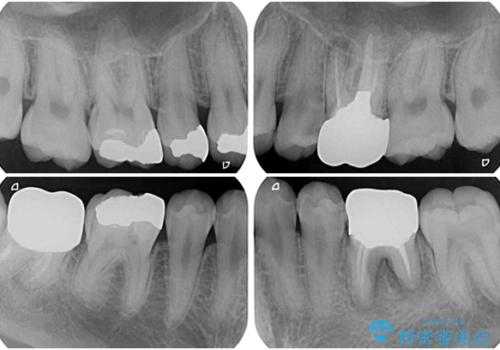

- 治療中の前歯と口腔内にある銀歯が気になるとのことで来院された患者様です。

土台に含まれている金属も含め、口腔内の金属は全て除去し、根管治療が必要な歯は根管治療を行い、オールセラミッククラウンやセラミックインレーにて治療することとしました。

途中来院されない時期があったため、初診から終了まで期間がかかりましたが、根管治療を行った歯の根尖病変はいずれも改善を確認することができました。